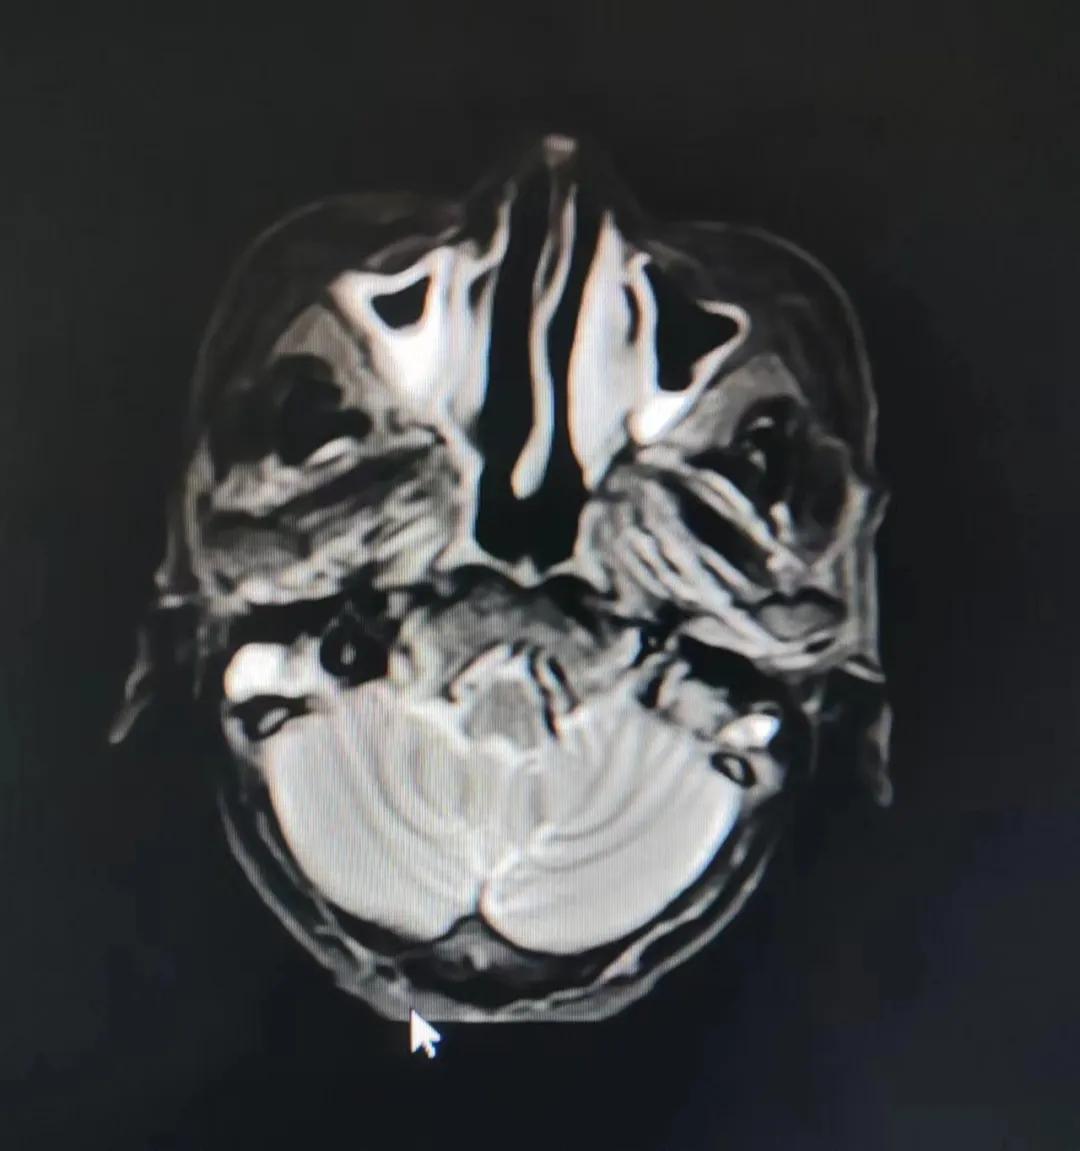

治療前

老人因鼻部腫物堵塞鼻腔并且侵犯鼻咽導(dǎo)致鼻塞、疼痛、吞咽困難,身心都備受煎熬,趙亮主任在詢問(wèn)其病史期間幾度落淚。趙亮主任向患者及家屬解釋說(shuō):“現(xiàn)代放療比過(guò)去的傳統(tǒng)放療設(shè)備先進(jìn),技術(shù)不斷提升,能對(duì)腫瘤區(qū)域的照射劑量進(jìn)行優(yōu)化,做到準(zhǔn)確定位、精準(zhǔn)照射,同時(shí),最大限度地降低正常組織的受量,對(duì)全身情況影響很小。”

考慮到患者年齡較大、體質(zhì)差,手術(shù)難度大,且常規(guī)的放射治療難以保護(hù)患者晶體造成患者雙眼視力損傷,放療團(tuán)隊(duì)以最快的速度制定了精準(zhǔn)放射治療方案并開(kāi)始為其實(shí)施治療。僅僅數(shù)日后,老人腫塊出血即得到控制,腫塊明顯縮小,放療20次后腫塊迅速縮??!